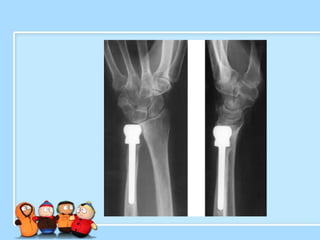

X-quang